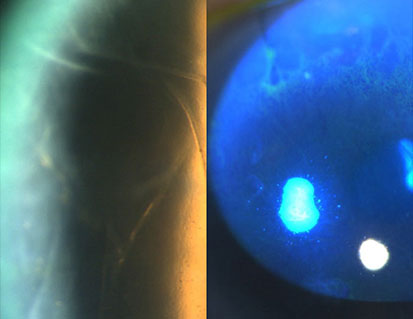

ANTERIOR SEGMENT STEM CELLS